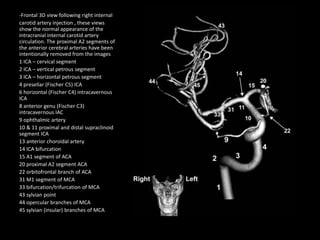

-Frontal 3D view following right internal

carotid artery injection , these views

show the normal appearance of the

intracranial internal carotid artery

circulation. The proximal A2 segments of

the anterior cerebral arteries have been

intentionally removed from the images

1 ICA – cervical segment

2 ICA – vertical petrous segment

3 ICA – horizontal petrous segment

4 presellar (Fischer C5) ICA

6 horizontal (Fischer C4) intracavernous

ICA

8 anterior genu (Fischer C3)

intracavernous IAC

9 ophthalmic artery

10 & 11 proximal and distal supraclinoid

segment ICA

13 anterior choroidal artery

14 ICA bifurcation

15 A1 segment of ACA

20 proximal A2 segment ACA

22 orbitofrontal branch of ACA

31 M1 segment of MCA

33 bifurcation/trifurcation of MCA

43 sylvian point

44 opercular branches of MCA

45 sylvian (insular) branches of MCA